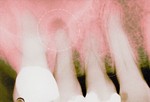

Пародонтоз.

При таком заболевании как гингивит, бактерии, которые аккумулируются в налете, провоцируют рецессию десневой линии и образование зубодесневого кармана. Через некоторое время начинается воспалительный процесс и происходит разрушение костной ткани. Тщательный уход за ротовой полостью служит залогом здоровых десен. Курение, плохое питание и стрессовые ситуации только ведут к ухудшению состояния зубов и десен. Следует немедленно обратиться к специалисту в случае рецессии десневой линии.